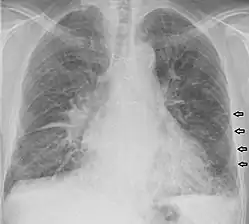

Kerley B lines in a patient with congestive heart failure.

Kerley B lines

These are short parallel lines at the lung periphery. These lines represent interlobular septa, which are usually less than 1 cm in length and parallel to one another at right angles to the pleura. They are located peripherally in contact with the pleura, but are generally absent along fissural surfaces. They may be seen in any zone but are most frequently observed at the lung bases at the costophrenic angles on the PA radiograph, and in the substernal region on lateral radiographs.[3] Causes of Kerley B lines include pulmonary edema, lymphangitis carcinomatosa and malignant lymphoma, viral and mycoplasmal pneumonia, interstitial pulmonary fibrosis, pneumoconiosis, and sarcoidosis. They can be an evanescent sign on the chest x-ray of a patient in and out of heart failure.